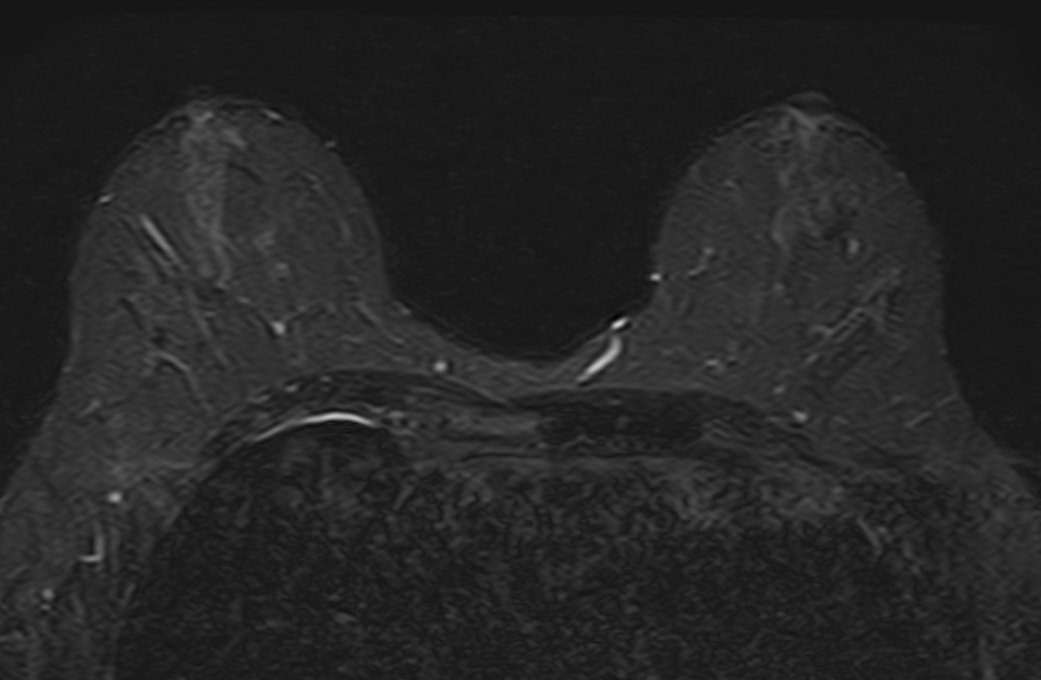

Выполнение МРТ молочных желез без контрастирования возможно для динамического наблюдения состояния имплантатов после пластической операции груди. Во всех остальных случаях во время проведения исследования внутривенно вводится контрастное вещество. Для контрастного усиления применяются препараты на основе солей гадолиния (Магневист, Гадовист и др).

Полученные во время исследования результаты сканирования при помощи компьютерной программы преобразуются в 3D-изображения, что дает детальную информацию о состоянии молочных желез и регионарных лимфоузлов.